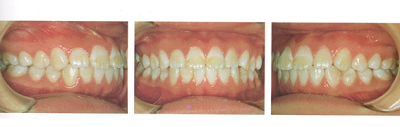

前回に引き続きアレキサンダー先生の術後評価から載せていきます。

彼女は術前の咬合状態には問題がなく、ただ顔貌の改善を目的として矯正治療を希望した。

治療後の側貌には大変満足しており、このような治療結果を望んで来院したのであるが、日本の矯正歯科の先生はどのように考えられるだろうか。

このような治療には価値がないと考えられるか、あるいは価値があると考えられるだろうか。

日本ではこの患者の術前のようなbimaxillary protrusionの傾向をもつ側貌は一般的で良く見かけるが、アメリカでは直線的な側貌を好む傾向が強いので、このような治療を患者が希望したものと思われる。

上の矯正前から下の矯正後で前歯の角度が変わったのが分かるでしょうか?